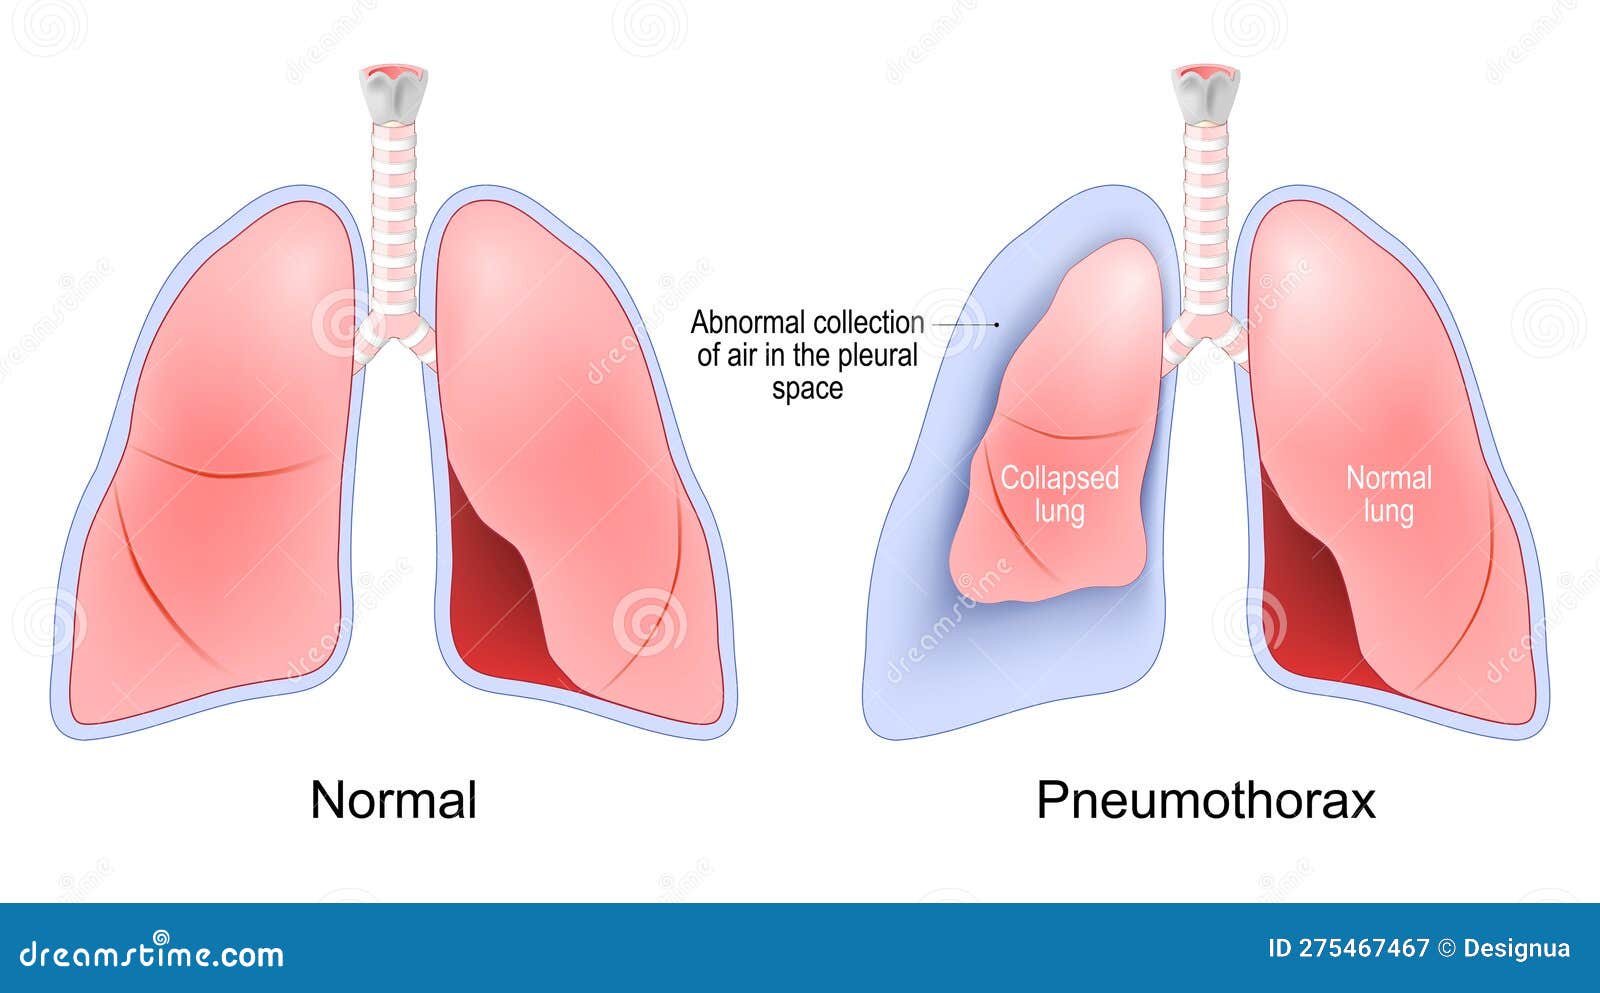

Схемы дыхания: Пневмоторакс на изображениях